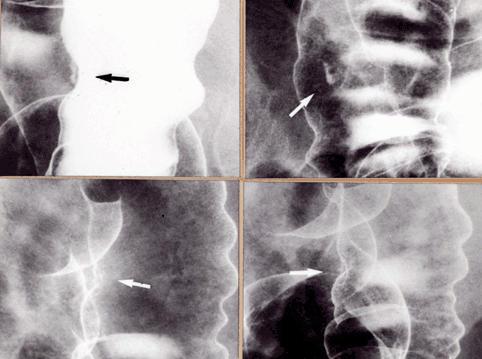

疾患(病理主体)の分類悪性上皮性腫瘍/腺癌

部位(臓器別)大腸/下行

検査方法X-P

腫瘍の肉眼分類0型(表在型)/IIc型(IIc)

病変の最大径(ミリ)1〜9

腫瘍の深達度m